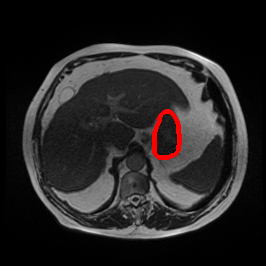

Ghosting Artifact

MRI GMAIMMbench Organ Recognition - Abdomen

Ghosting Artifact - L0 (Original)

L0 (Original)

Ghosting Artifact - L1 (Moderate)

L1 (Moderate)

Ghosting Artifact - L2 (Severe)

L2 (Severe)

Question

Observe the MRI image. Can you identify the organ in the highlight area?

A fat B stomach C optic cup D gallbladder E optic disc

Ground Truth: B. stomach